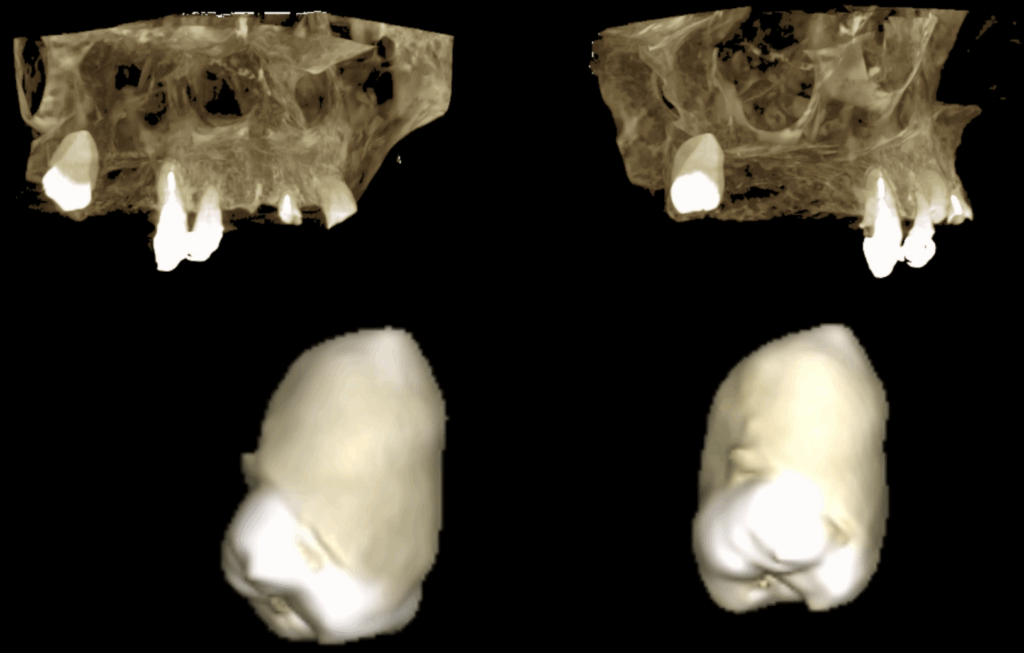

En las reconstrucciones 3D se representa de manera  idáctica Hipercementosis y Anquilosis (Pieza Dentaria 18) (Figura 4).

RECONSTRUCCIÓN 3D